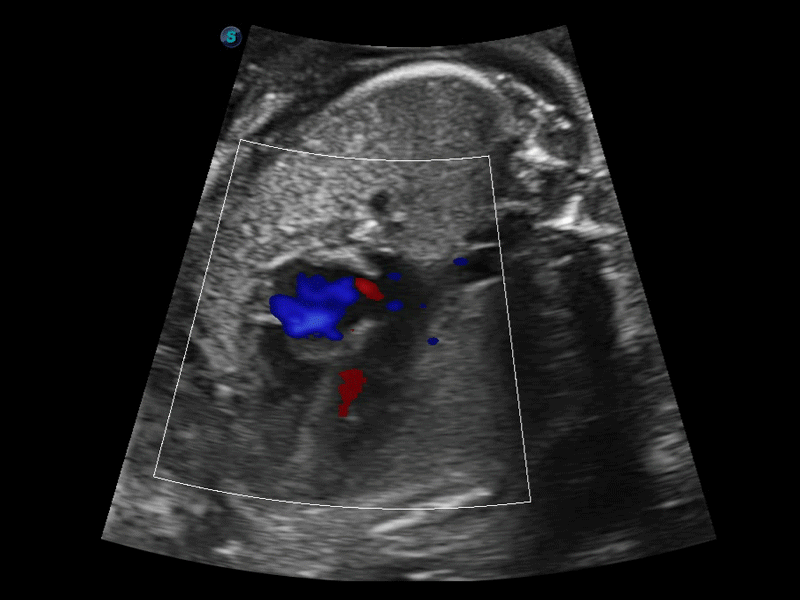

開立醫(yī)療通過不斷的技術(shù)創(chuàng)新,為大眾的生命健康提供持續(xù)關(guān)愛。P12 Plus采用全新一代超聲成像平臺,新平臺旨在將真實(shí)還原組織解剖結(jié)構(gòu)作為首要目標(biāo)。平臺采用全新集成化硬件模塊,搭載新一代芯片,系統(tǒng)性能得到大幅提升,為您的診斷提供了豐富的臨床信息。優(yōu)異的圖像表現(xiàn),豐富的探頭配置,全面的應(yīng)用功能,為您日常診斷提供了可靠的助手。

P12 Plus

彩色多普勒超聲診斷系統(tǒng)